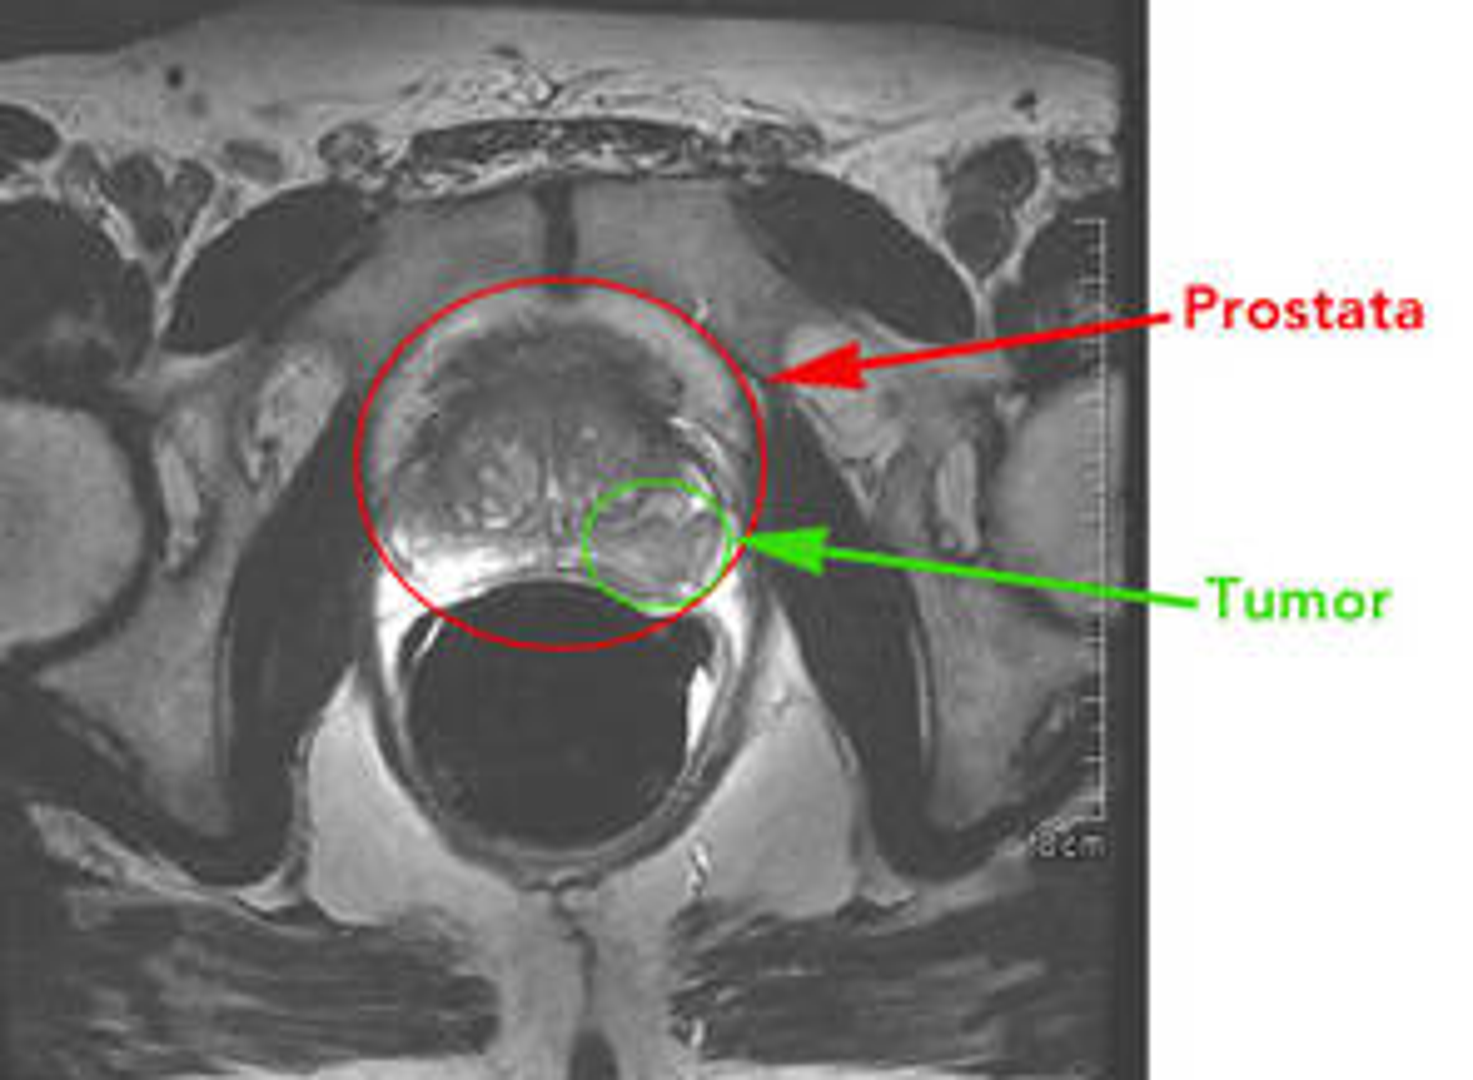

U ranim fazama rak prostate često ne  izaziva nikakve simptome tijekom mnogo godina. Često se kao prva nenormalnost pojavi povišena vrijednost PSA u krvi ( PSA= prostata specifični antigen, objašnjeno u nastavku) ili tvrda kvržica u prostati tijekom tzv. digitorektalnog pregleda. Prostata se anatomski nalazi neposredno ispred rektuma pa uvlačenje prsta u završno crijevo i pipanje prostate kroz stijenku crijeva daje odgovor koliko je prostata velika, kakve je strukture i konzistencije, postoji li razlika između desnog i lijevog režnja i kakva je granica između tih režnjeva.

Faza II (ili B): Tumor je veći  nego u fazi I i može se napipati kod digitorektalnog pregleda.  Nema dokaza da se rak proširio izvan prostate. Ovakav nalaz obično se utvrdi biopsijom prostate kad muškaraca s povišenom razinom PSA.